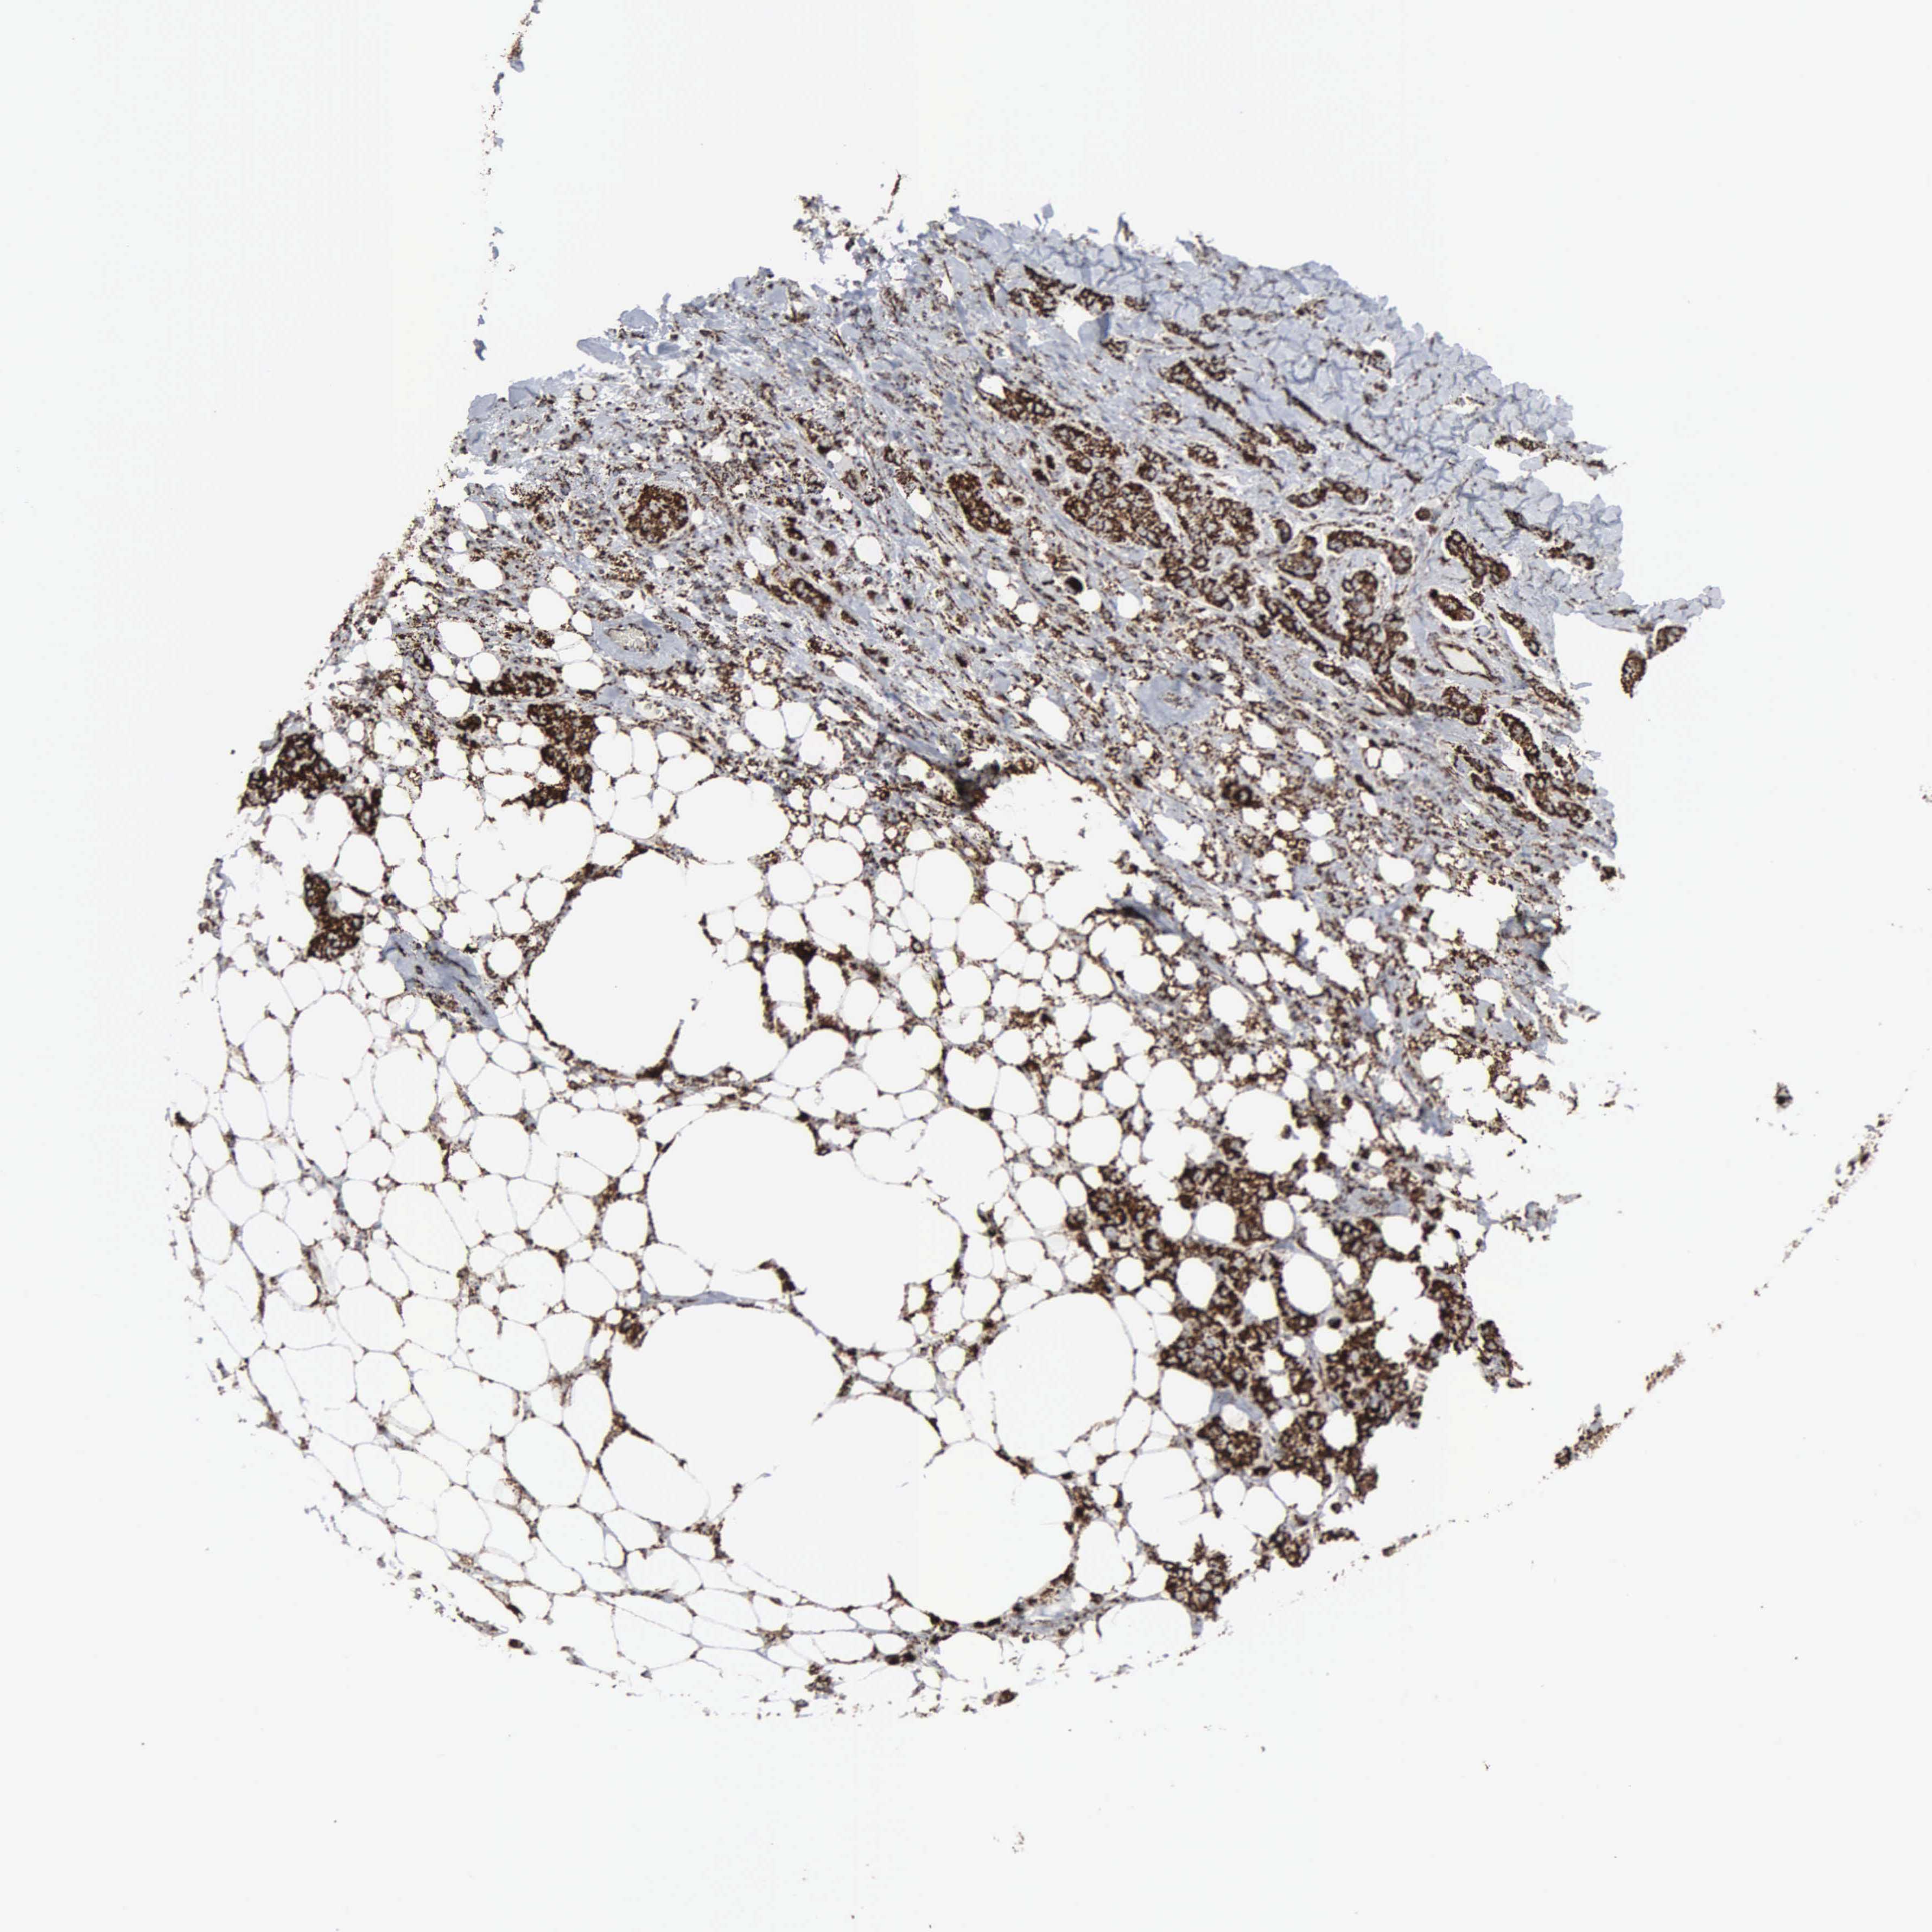

BRCA TCGA BRCA VALIDATION PROTEIN EXPRESSION

ANTIBODIES

AND

VALIDATION